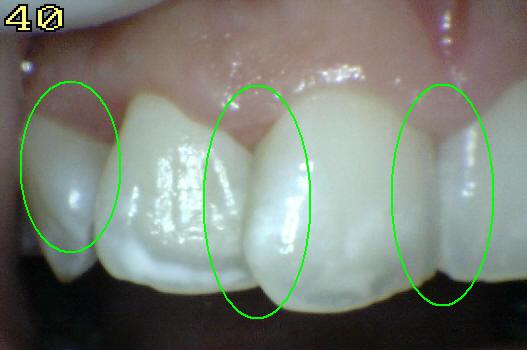

Código 3

(Caries Moderada): Ruptura

localizada del esmalte debido a caries sin dentina visible.

-

La superficie seca muestra una perdida detectable de la

estructura del esmalte. El diente visto en estado

húmedo pueden tener una clara opacidad de caries (mancha blanca

/ marrón)

Una

sonda paeriodontal puede deslizarse sobre la

lesión para comprobar micro-cavidad (pérdida de la

integridad de la superficie de esmalte < 0,5 mm.)